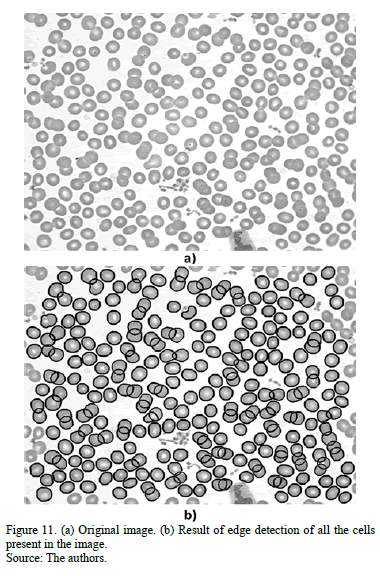

The final output looks like the one in Fig. 11, which shows that the algorithm also manages to classify groups of more than three cells. In addition, Fig. 12 shows comparative results for three different algorithms: a watershed approach, an algorithm using the Hough transform, and our method. The Hough-based algorithm was superior to the watershed approach, but it still could not identify cells with no circular shape. In contrast, our algorithm performs better in cells with an irregular shape, and does not present over-segmentation as the watershed-based algorithm does.